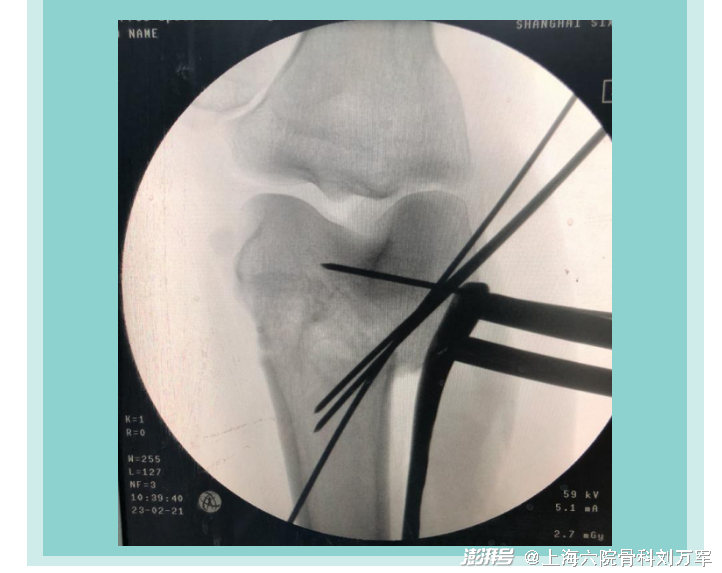

02治疗过程

DFO截骨手术是通过纠正下肢力线来重新均衡内外间室的载荷,从而达到缓解疼痛,重建关节功能的目的。